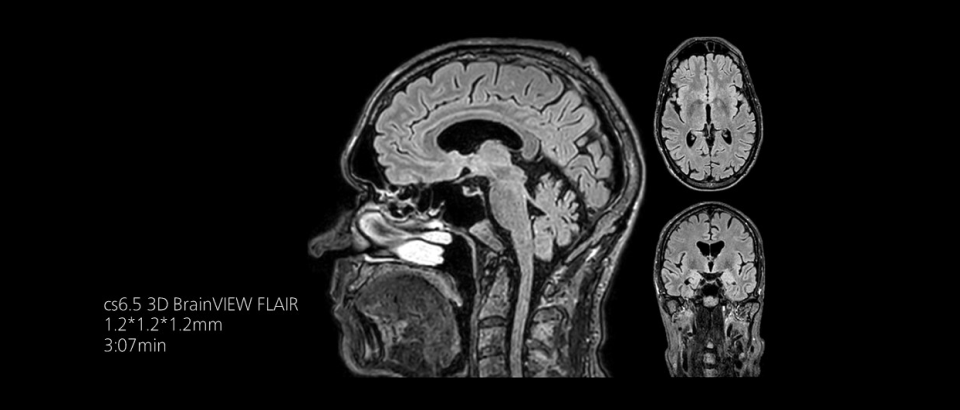

Compressed SENSEは、実質的に同等の画質を保ちつつ、撮像時間を最大50%²高速化します。

時間を味方につける - Compressed SENSEを使用すると、実質的に同等の画質を保ちつつ、撮像時間を最大50%²短縮できます。空間分解能が60%向上した高品質のMR画像を得ることで確実な診断が可能になります。